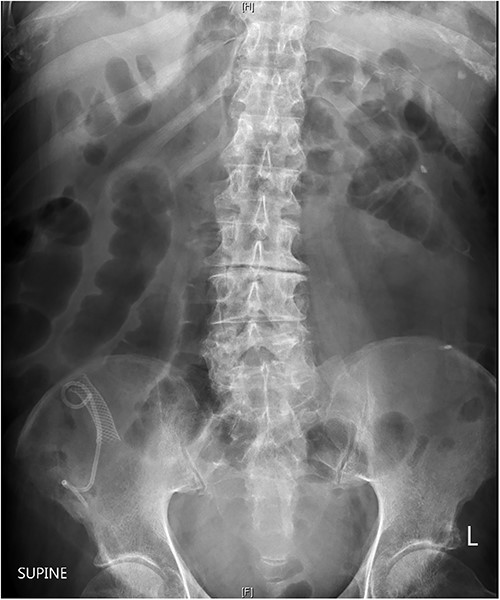

After a multidisciplinary consultation involving medical, geriatrics and surgical teams, the patient and family collectively decided for conservative management given age and high-risk multiple comorbidities. He was managed with intravenous fluids, broad spectrum Gram positive and Gram negative intravenous antibiotics, nasogastric tube and an indwelling catheter for 48 h. He progressed with minimal pain over the next 24 h and passed flatus. Subsequent plain abdominal radiography 2 days after presentation confirmed the presence of migrated metal and plastic biliary stents in the terminal ileum with dilated loops of small bowel suggestive of ongoing bowel obstruction (Fig. 3). After 5 days of not opening bowels and ongoing pain, he was transferred back to a nursing home facility with palliative care services in place. The patient passed away 3 weeks after transferring back to the nursing home facility with a suspected bowel perforation and no documentation of the stents having been passed.

Abdominal radiography showing plastic and metallic biliary stents projected over the right iliac bone and dilated loops of small bowl throughout the abdomen and pelvis.